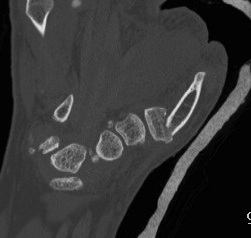

B. Rolando Fracture

Fracture

- 2 small intra-articular fragments

- poor prognosis